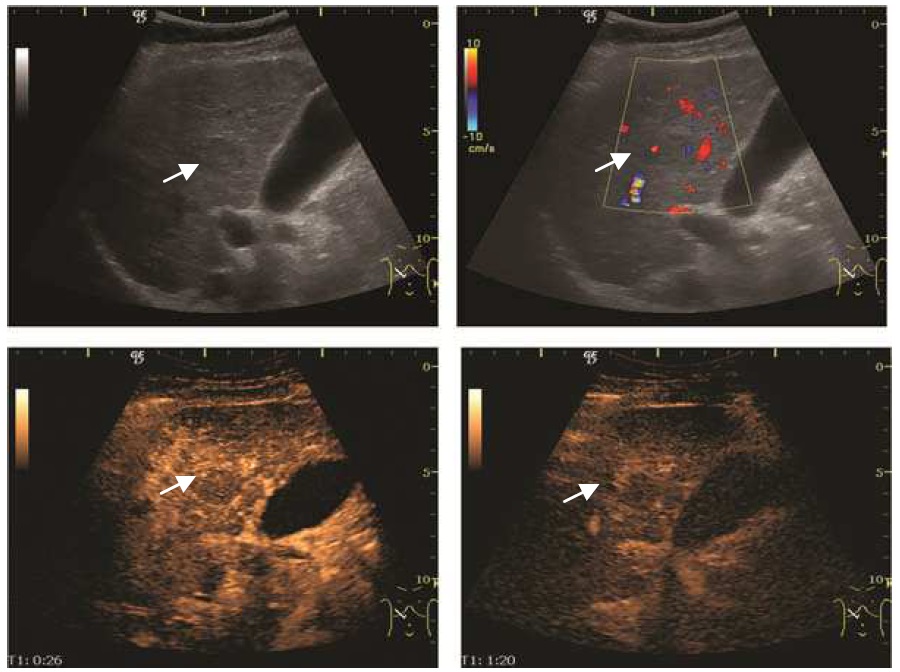

Метастатические поражения печени в ультразвуковом изображении характеризуются